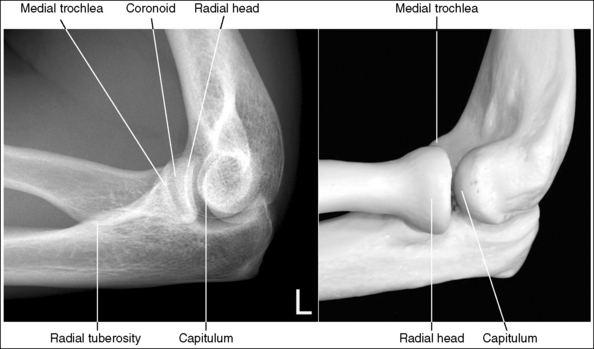

The elbow is in a lateral projection. The distal humerus demonstrates three concentric arcs, which are formed by the trochlear sulcus, capitulum, and medial trochlea. The elbow joint space is open, and the radial head is superimposed over the coronoid process.

• A lateral elbow projection is obtained when the humeral epicondyles are positioned directly on top of each other, placing an imaginary line drawn between them perpendicular to the IR. To obtain this humeral epicondyle positioning, place the humerus parallel with the IR and elevate the distal forearm until the palpable medial and lateral epicondyles are superimposed (Figure 4-78). This positioning aligns the trochlear sulcus, capitulum, and medial trochlea into three concentric (having the same center) arcs (Figure 4-79). The trochlear sulcus is the small center arc. It moves very little when a positional change is made and works like a pivoting point between the capitulum and medial aspect of the trochlea. The largest of the arcs is the medial aspect of the trochlea. It is demonstrated very close to and slightly superimposed on the curve of the trochlear notch. The intermediate-sized arc is the capitulum. When these three arcs are in accurate alignment, the elbow joint is visualized as an open space and the anterior and proximal surfaces of the radial head and coronoid process are aligned.

Figure 4-79 AP (left) and lateral (right) images showing anatomy of the distal humerus. (From Martensen K III: The elbow, In-Service Reviews in Radiologic Technology, 14[11], 1992.)